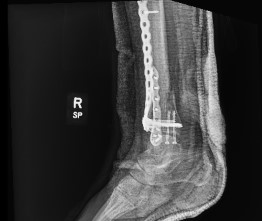

Status post ORIF with plate and screws in the distal fibula and tibia with 2 screws in the medial malleolus. A portion of the fracture line is still evident in the tibia.

Radiographs and CT scan confirmed healing fractures with a congruent mortise, but hardware impingement on dorsiflexion and eversion.

Status post ORIF with plate and screws in the distal fibula and distal tibia with healed fracture of the distal shaft of the tibia with mild deformity with anatomic alignment maintained.Healed fracture of the distal fibula without residual deformity.

Healed medial malleolus fracture without deformity.